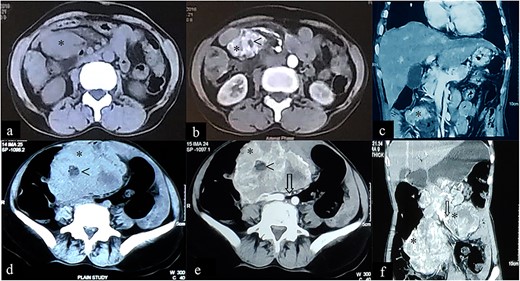

A 50-year-old female presented with a 2-year history of intermittent left flank pain occurring once every 1–2 months with each episode lasting for 6–7 days, which sometimes required analgesics. She also complained of gradually increasing anorexia, as well as abnormal stool consistency. The patient was previously seen at another facility 12-month earlier where a CECT of the abdomen showed a cystic lesion (8.98 × 5.34 cm) with enhancing wall, septa and a solid component (28 × 13 mm) in the left abdominal cavity abutting the jejunum anteriorly, psoas muscle posteromedially and the small bowel both superiorly and inferiorly, suggestive of an EGIST (Fig. 3 a–c). She initially opted for conservative treatment but her symptoms worsened and hence she visited to our outpatient clinic for further management.

Case 2: CT imaging of Extragastrointestinal stromal tumor. (a) Non-contrast axial; (b, c) contrast enhanced axial and coronal reformatted CT images of abdomen demonstrates intraperitoneal cystic lesion (*) with eccentric enhancing solid component (<) abutting kidney and bowel. (d) Non-contrast axial; (e, f) contrast enhanced axial and coronal reformatted CT images of abdomen of same patient after 1-year interval follow up demonstrates increased size of the lesion (*).

On presentation she was alert and oriented with no acute distress and normal vital signs. Her physical examination was unremarkable except for her abdominal findings, which revealed a soft, non-distended abdomen with a lower midline surgical scar, no striae, dilated veins, rashes or visible peristalsis. Bowel sounds and rectal exam were normal. A fixed mass (12 cm × 8 cm) was appreciated in the left-upper quadrant. A complete blood count, renal function test, liver function test and coagulation profile were all normal. Repeat CECT of the abdomen and pelvis showed an intraperitoneal cystic lesion (83 × 80 × 59 mm) with an eccentric enhancing solid component (73 × 29 mm) within the mesentery abutting an area from the distal duodenum to the jejunal loop inferiorly with features suggestive of an EGIST (Fig. 3d–f).